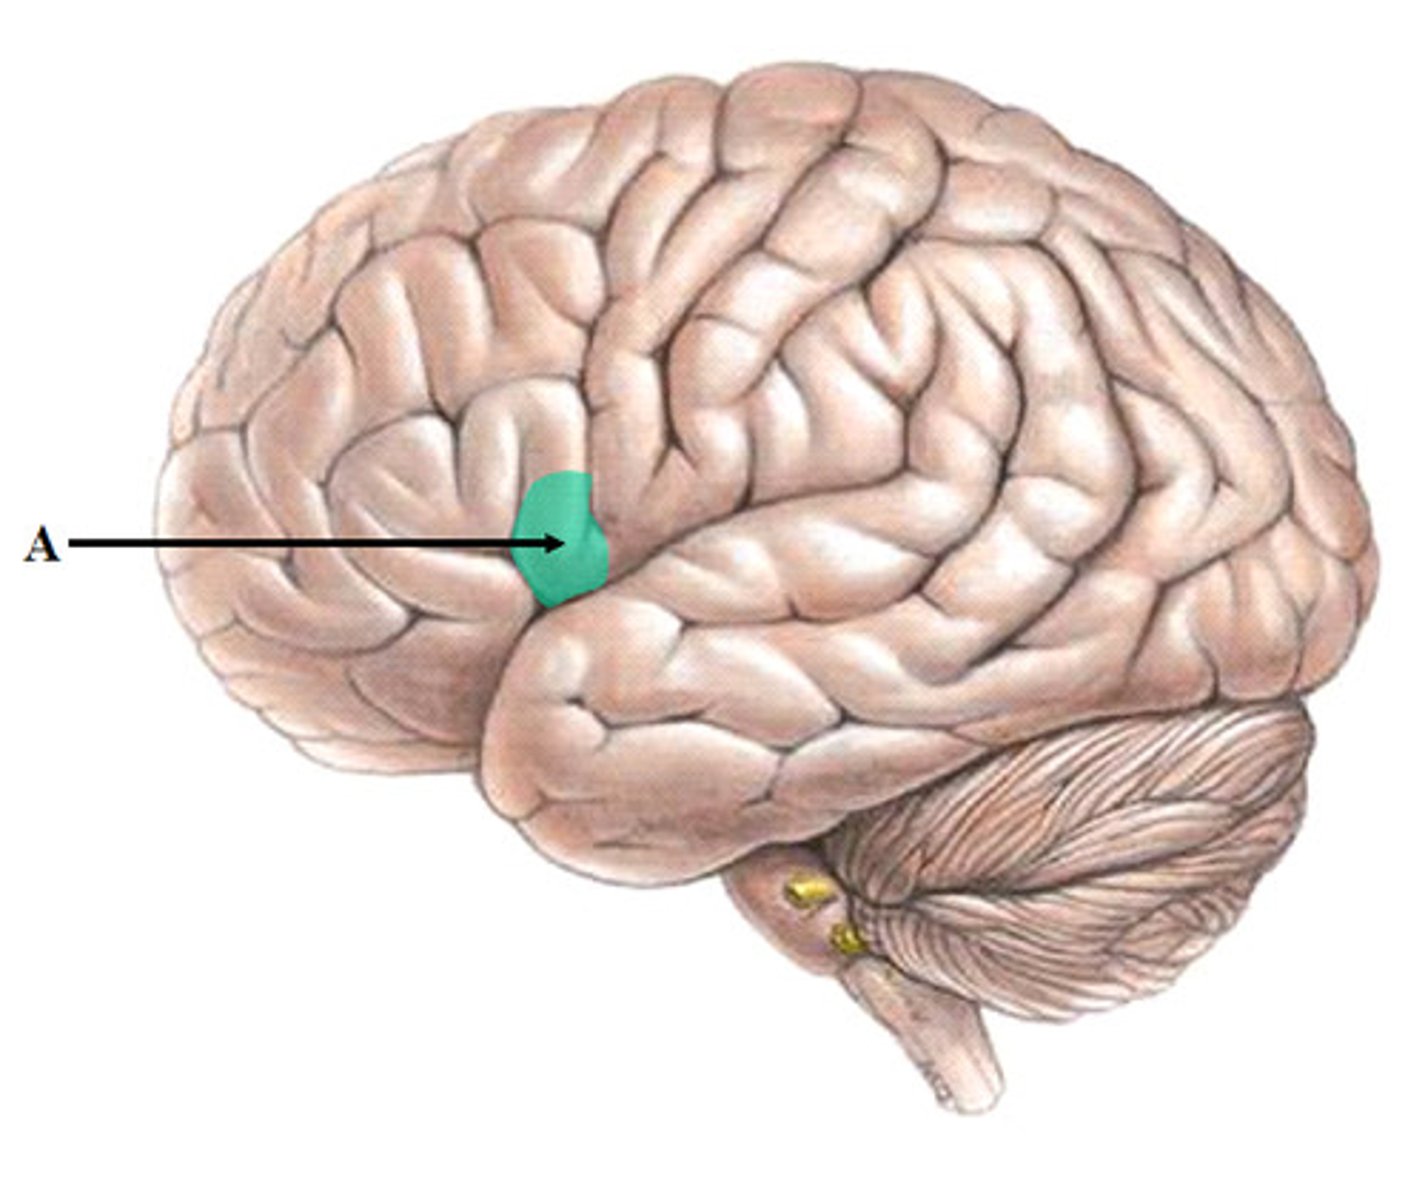

broca's area

speech production